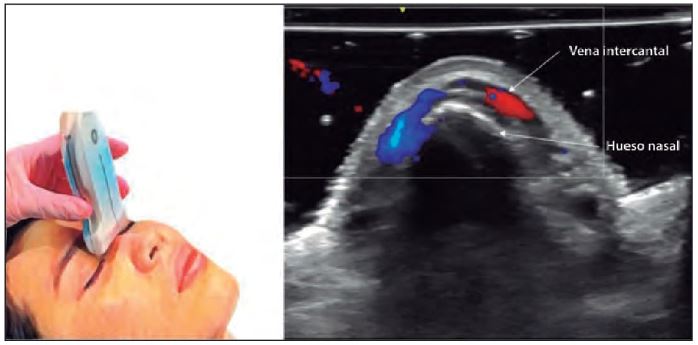

Un conocimiento profundo de la anatomía nasal es indispensable para realizar procedimientos seguros. La ecografía permite visualizar:

- Capas de tejido: Epidermis, dermis, hipodermis, SMAS, huesos y cartílagos.

- Estructuras vasculares: Arterias como la angular, nasal lateral y ramas de la arteria oftálmica.

- Modos B y Doppler en color: Para evaluar estructuras anatómicas y flujo vascular.